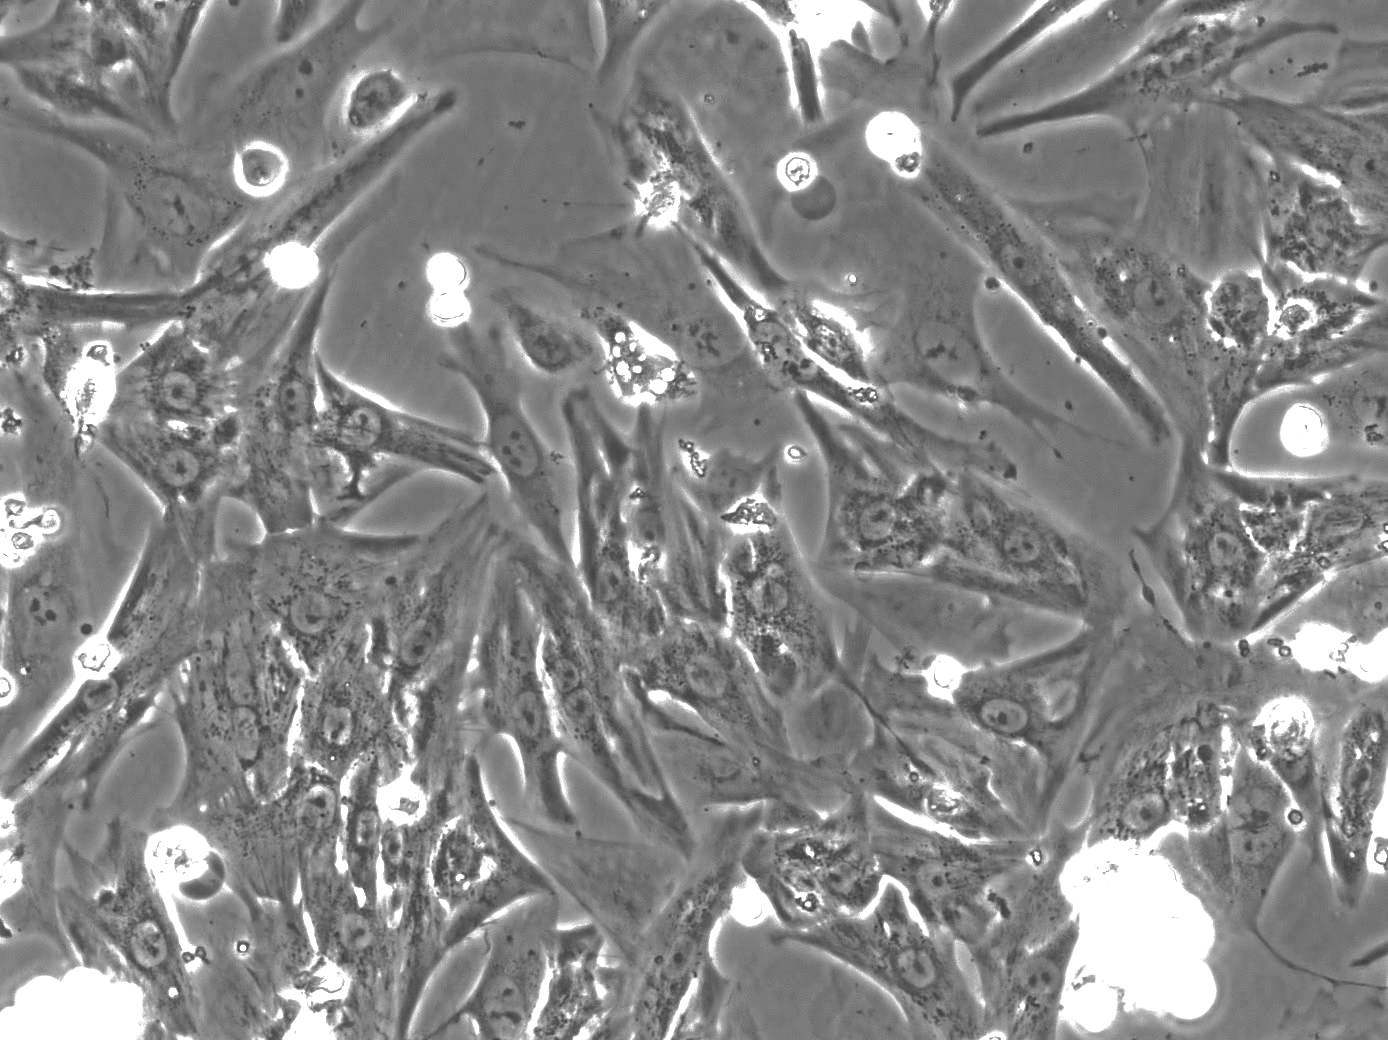

Nemške raziskovalke in raziskovalci so ustvarili gel iz kolagena, alginata in elektrokonduktivnega polimera. Kolagen je glavna beljakovina vezivnega tkiva pri živalih, alginat je polisaharid, ki ga pridobivamo iz rjavih alg in se veliko uporablja v tkivnem inženirstvu za pripravo gelov, elektrokonduktiven polimer pa naredi gel električno prevoden. V tem gelu so znanstveniki gojili podganje neonatalne srčnomišične celice. Primerjali so jih z enakimi celicami, ki so rasle v gelu, pripravljenem le iz kolagena in alginata. V gelu z elektrokonduktivnim polimerom so celice boljše rasle in se diferencirale. Ker so bile med seboj električno sklopljene, so se tudi usklajeno krčile. V gelu s polimerom so celice dosegle tudi višjo frekvenco utripanja in utripale več dni kot v kontrolnem gelu.